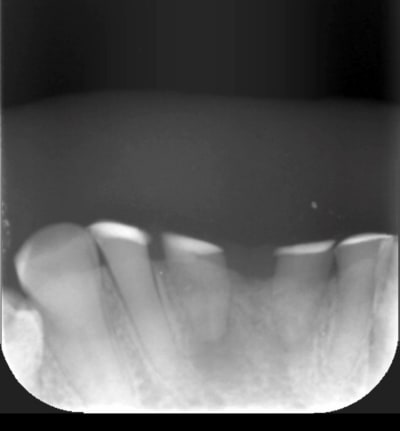

Radio 26

D9f30056 befd 4a58 a9d3 44fed132d3d4 zi8p3v - Eugenol

poignée de porte a diagnostiqué une maladie genetique, c'est un cas d'amélogenèse imparfaite avec racines courtes, obliteration des chambres pulpaires, émail fin et de mauvaise minéralité pour du collage... necrose en lien avec l'usure (les incisives inf)